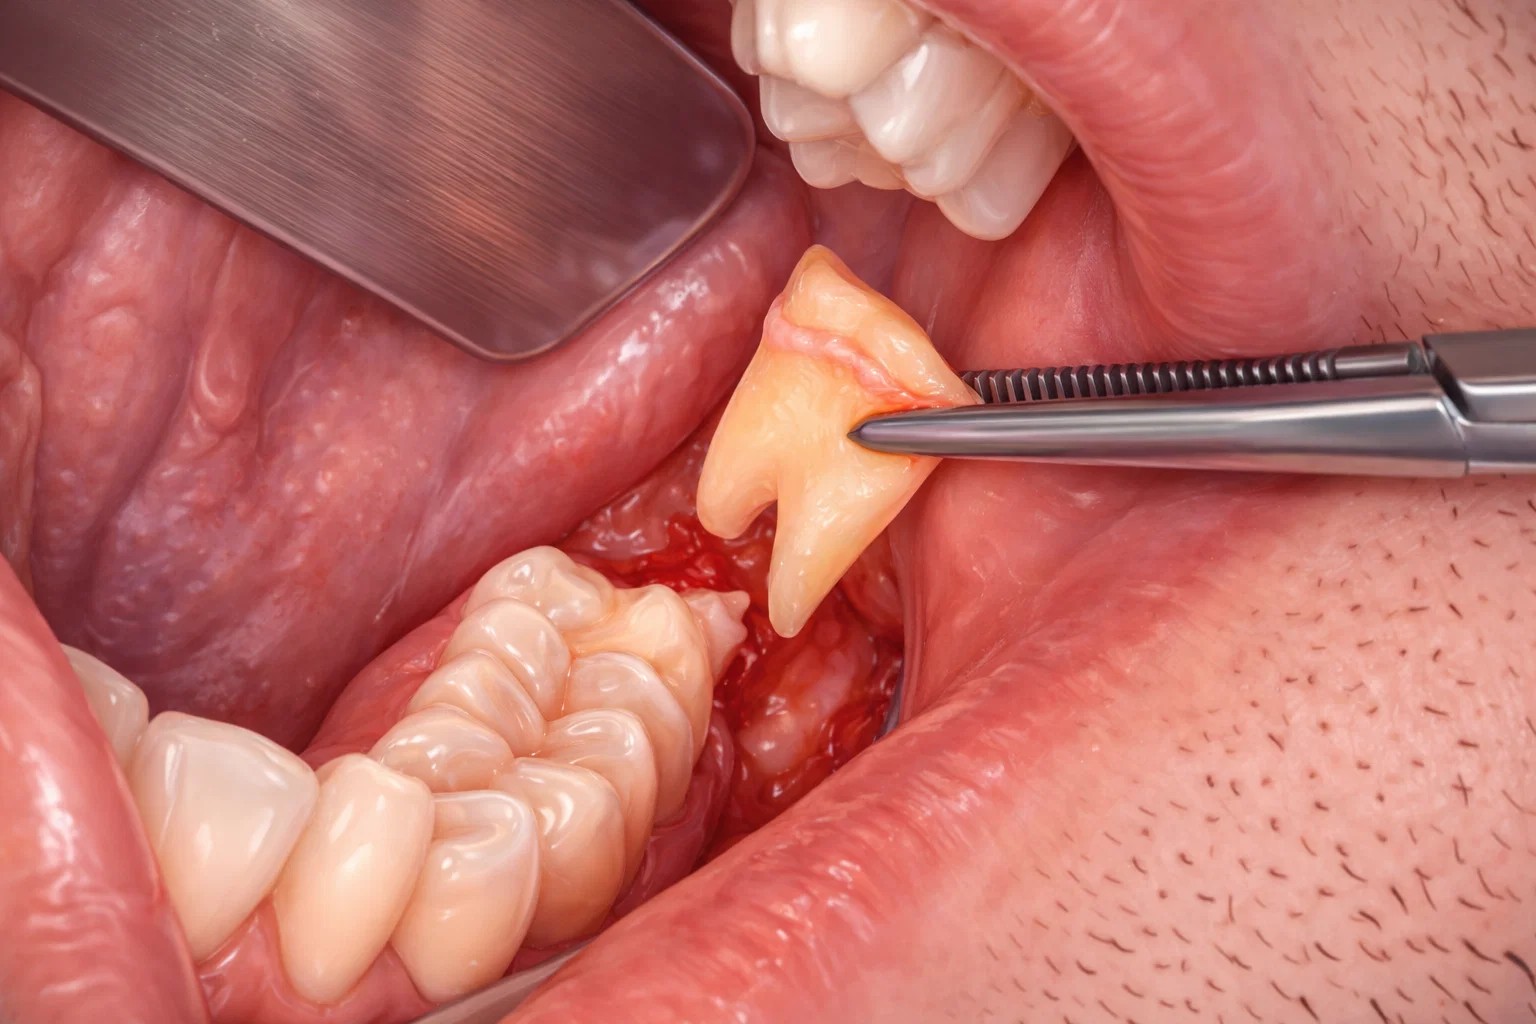

서울 치과 안전한 발치를 위한 핵심, ‘치아 분리 기법’

완전 매복되거나 누워있는 사랑니는 주변 턱뼈의 삭제를 최소화하기 위해 치아를 여러 조각으로 나누어 배출하는 ‘치아 분리 기법’을 적용합니다. 이는 무리하게 치아를 뽑아내려다 발생할 수 있는 턱뼈의 과도한 손상과 신경 압박을 방지하는 정교한 술식입니다.

치아 머리와 뿌리를 단계별로 분리하여 한 조각씩 부드럽게 제거함으로써 수술 후 통증과 부기를 획기적으로 줄일 수 있습니다. 믿음가는치과에서는 최소한의 골삭제만으로 정확하게 사랑니를 발치하여 환자분의 신체적 부담을 덜어드립니다.